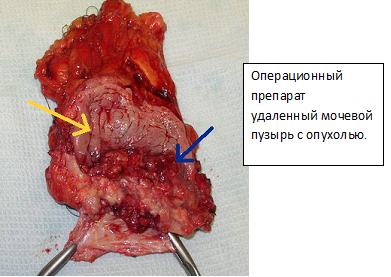

Еще одна достаточно типичная картина рака мочевого пузыря, видимая при цистоскопии:

Инвазивный рак предполагает лечение методом радикальной цистэктомии с расширенной лимфодисскецией. Дополнением к лечению могут служить: